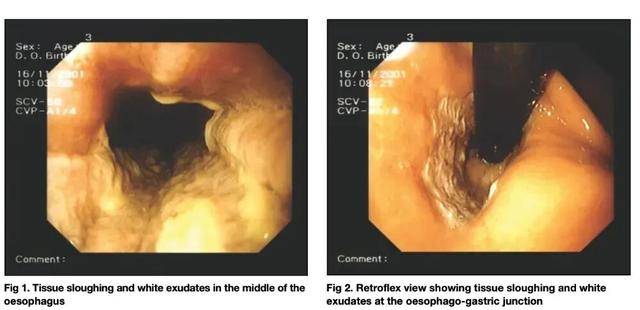

另一个广泛流传的方法,是喝醋软化鱼刺。但医学证据恰恰相反。一项病例报告显示,饮用普通食用醋不仅不能溶解鱼刺,反而可能造成口咽和食管的腐蚀性损伤[4]。这类损伤在内镜下表现为明确的黏膜炎症甚至溃疡,而鱼刺往往并未因此消失。

患者黏膜出现组织脱落和白色渗出物 图源:参考资料